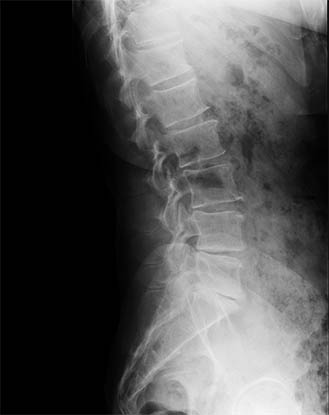

Impulse su productividad del procesamiento con el Procesamiento de Visualización Mejorado (Enhanced Visualization Processing, EVP) Plus. Aumenta la eficiencia de la obtención de aspectos preferidos al utilizar controles de parámetros mutuamente independientes, proporciona varios aspectos preconfigurados y permite personalizar los aspectos según las preferencias del sitio. EVP Plus proporciona un mejor control de ruido, nitidez, contraste y densidad a la vez que reduce los artefactos.